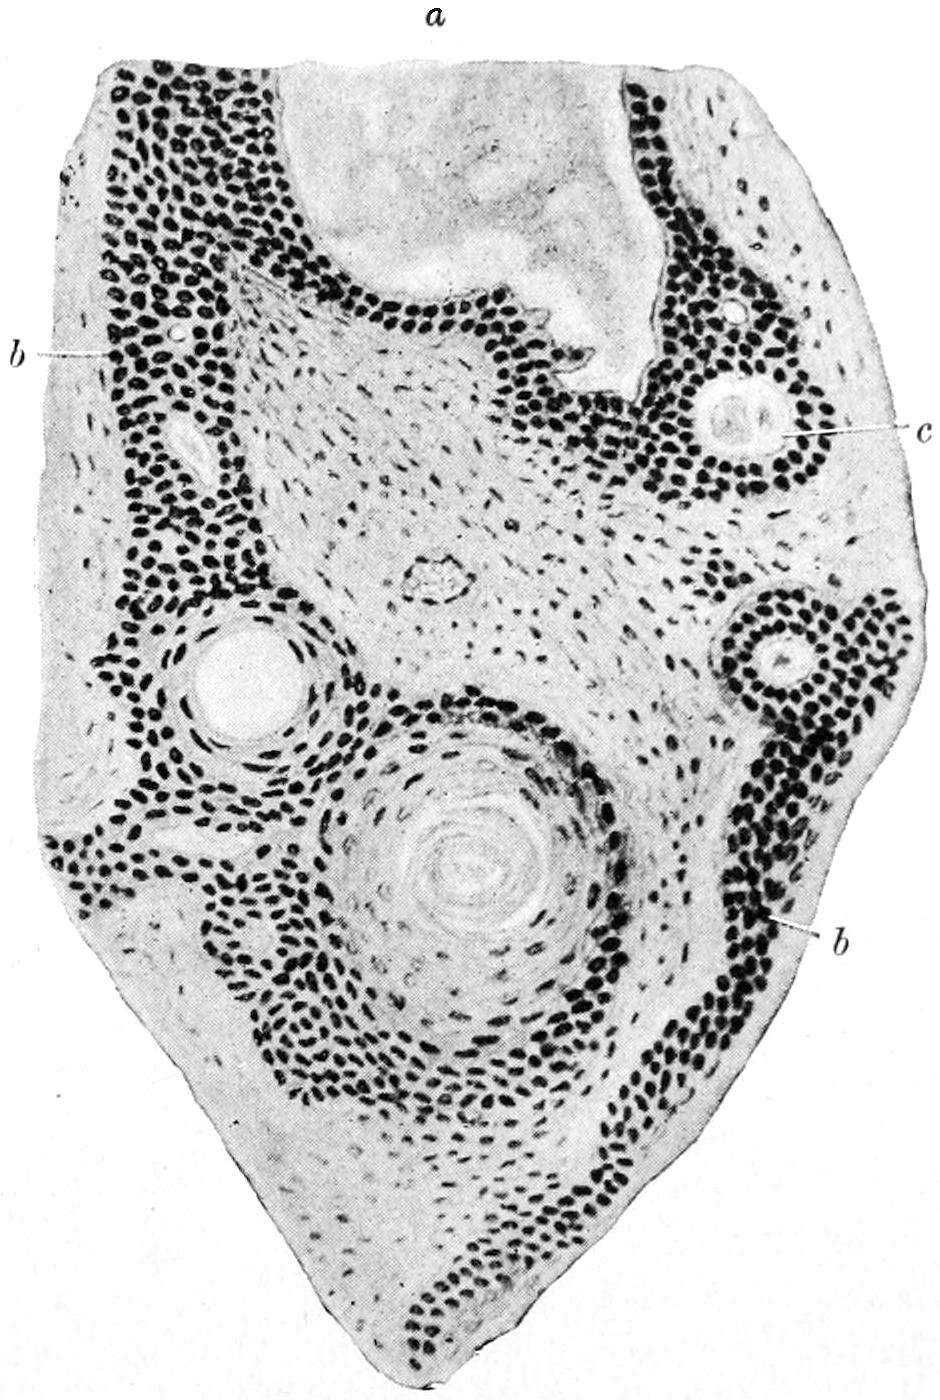

PLATE I

PLATE I.

BLOOD.

(Ehrlich triple stain.)

Fig. I. TYPES OF LEUCOCYTES.

a. Polymorphonuclear Neutrophile. b. Polymorphonuclear Eosinophile. c. Myelocyte (Neutrophilic). d. Eosinophilic Myelocyte. e. Large Lymphocyte (large Mononuclear). f. Small Lymphocyte (small Mononuclear).

Fig. II. NORMAL BLOOD.

Field contains one neutrophile. Reds are normal.

Fig. III. ANÆMIA, POST-OPERATIVE (secondary).

The reds are fewer than normal, and are deficient in hæmoglobin and somewhat irregular in form. One normoblast is seen in the field, and two neutrophiles and one small lymphocyte, showing a marked post-hæmorrhagic anæmia, with leucocytosis.

Fig. IV. LEUCOCYTOSIS, INFLAMMATORY.

The reds are normal. A marked leucocytosis is shown, with five neutrophiles and one small lymphocyte. This illustration may also serve the purpose of showing the leucocytosis of malignant tumor.

Fig. V. TRICHINOSIS.

A marked leucocytosis is shown, consisting of an eosinophilia.

Fig. VI. LYMPHATIC LEUKÆMIA.

Slight anæmia. A large relative and absolute increase of the lymphocytes (chiefly the small lymphocytes) is shown.

Fig. VII. SPLENO-MYELOGENOUS LEUKÆMIA.

The reds show a secondary anæmia. Two normoblasts are shown. The leucocytosis is massive. Twenty leucocytes are shown, consisting of nine neutrophiles, seven myelocytes, two small lymphocytes, one eosinophile (polymorphonuclear) and one eosinophilic myelocyte. Note the polymorphous condition of the leucocytes, i. e., their variations from the typical in size and form.

Fig. VIII. VARIETIES OF RED CORPUSCLES.

a. Normal Red Corpuscle (normocyte). b, c. Anæmic Red Corpuscles. d-g. Poikilocytes. h. Microcyte. i. Megalocyte. j-n. Nucleated Red Corpuscles. j, k. Normoblasts. l. Microblast. m, n. Megaloblasts.

The value of a careful blood examination is well illustrated by Plate I, prepared by Dr. Irving P. Lyon, in which are displayed the alterations of greatest interest to the surgeon.